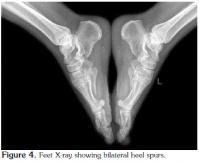

The bilateral knee radiographs of the patient were normal (Figure 2), but those of the feet revealed osteodegenerative changes (Figure 3) and bilateral heel spurs (Figure 4).